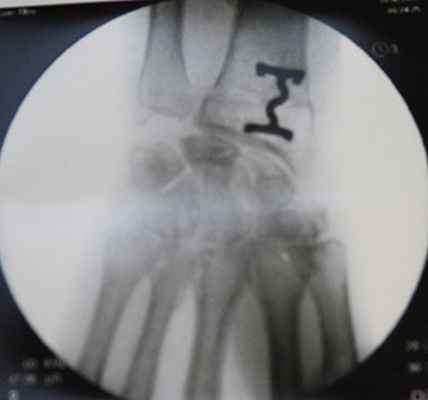

Снимок после укорочения лучевой кости

Элегантный способ фиксации остеотомии скобкой.

Вернемся к нашей героине, которая столкнулась с проблемой запястья накануне свадьбы. За месяц до намеченной даты была выполнена операция — остеотомия лучевой кости.